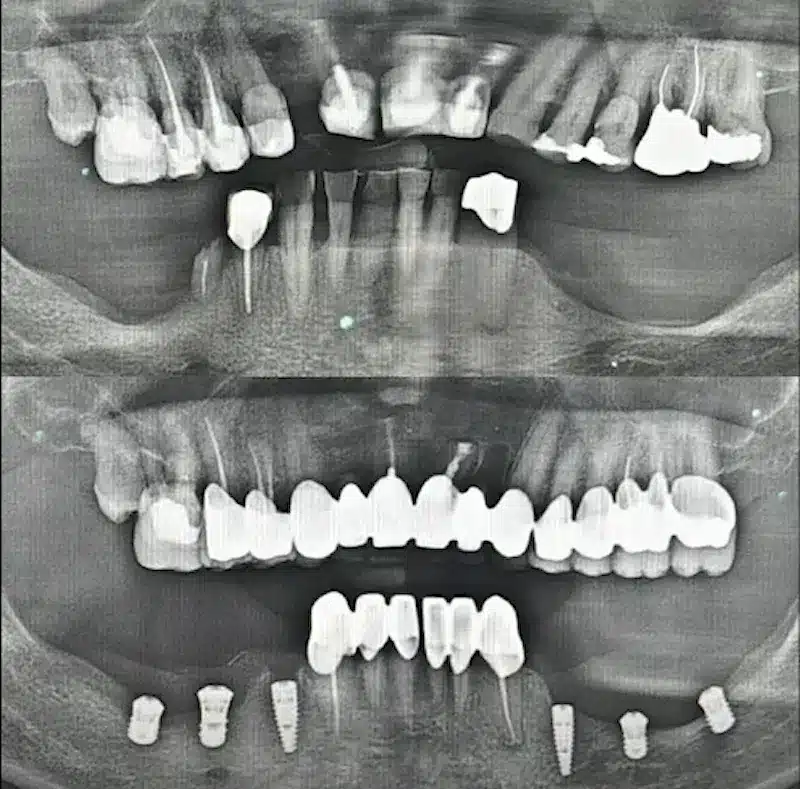

Dr. Seden Aksu is a specialist in modern implantology and surgical dentistry with extensive experience in the management of complex clinical cases. In her practice, she applies comprehensive surgical planning, minimally invasive techniques, and advanced regenerative technologies aimed at restoring both the function of the dentoalveolar system and the aesthetics of the smile. Dr. Aksu has significant experience in performing implant procedures, bone augmentation, and periodontal surgery, including the treatment of patients with severe bone loss. The primary goal of her work is to achieve stable, long-term outcomes in implant rehabilitation and the restoration of oral tissue health.